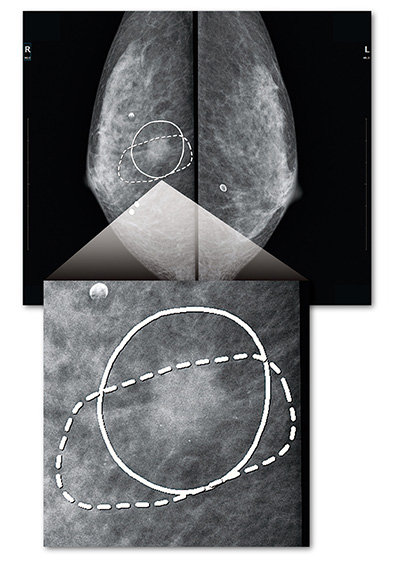

CAD:DICOM SRに対応し、CADシステムで生成されたCADの表示が可能です。ワンクリックで表示/非表示を実行し、読影を支援します。